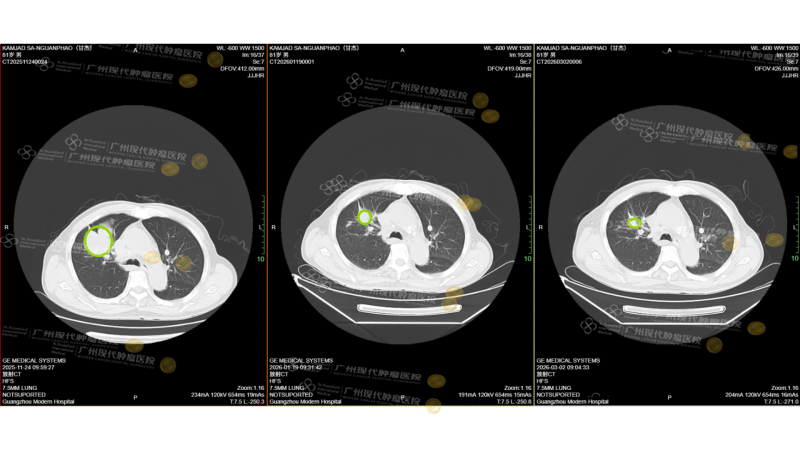

Hiệu quả đạt được thật sự ấn tượng: trước điều trị, khối u phổi phải của ông Kamjad khoảng 69 × 47 mm; chỉ sau hai liệu trình, tổn thương đã giảm mạnh còn 33 × 23 mm, thu nhỏ gần 50%! Đồng thời, các ổ di căn gan cũng co nhỏ rõ rệt, với tổn thương lớn nhất giảm từ 37 × 32 mm xuống còn 24 × 21 mm.

Những thay đổi rõ rệt trên hình ảnh học cho thấy gánh nặng khối u đã giảm đáng kể, hiệu quả điều trị vượt xa mong đợi.